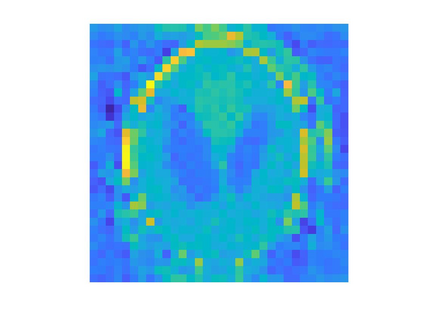

While Computerized Tomography (CT) images can help detect disease such as Covid-19, regular CT machines are large and expensive. Cheaper and more portable machines suffer from errors in geometry acquisition that downgrades CT image quality. The errors in geometry can be represented with parameters in the mathematical model for image reconstruction. To obtain a good image, we formulate a nonlinear least squares problem that simultaneously reconstructs the image and corrects for errors in the geometry parameters. We develop an accelerated alternating minimization scheme to reconstruct the image and geometry parameters.